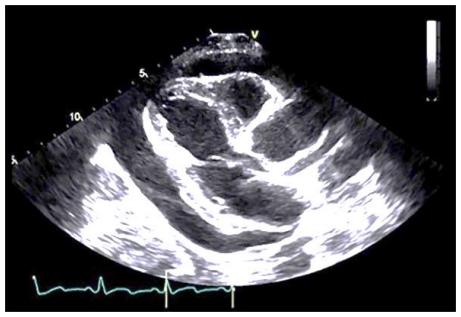

Homem de 78 anos, 75kg e 1,70m, hipertenso e diabético, se apresenta na emergência cardiológica com dor torácica forte, sendo indicada cineangiocoronariografia. Exames laboratoriais evidenciaram ureia de 200mg/dL-1, creatinina de 3,2mg/dL-1, potássio de 5,5mEq/L-1 e hemoglobina de 9,2g/dL-1. O ecocardiograma revela a seguinte imagem:

Durante o transporte para a radioscopia, o paciente evoluiu com baixa da consciência, sudorese e hipotensão arterial. O uso de vasopressores não melhorou a situação cardiovascular. Diante desse quadro, a conduta a ser tomada deve ser: